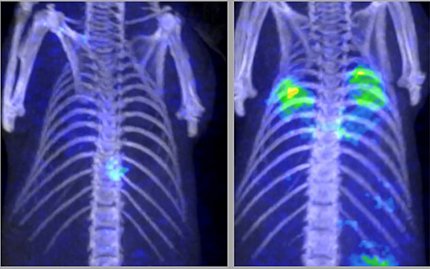

The radiolabeled cellobiose was eventually proven in animal models to be a specific imaging ligand for certain invasive fungi like Aspergillus.

After so many failed attempts with other sugars, when Hammoud and her lab finally saw high radioactive signal localizing to the fungal infection on PET after injecting the tagged cellobiose, they thought it must be a fluke. But it was the breakthrough they were hoping for. She and Swenson published their work in August 2024.